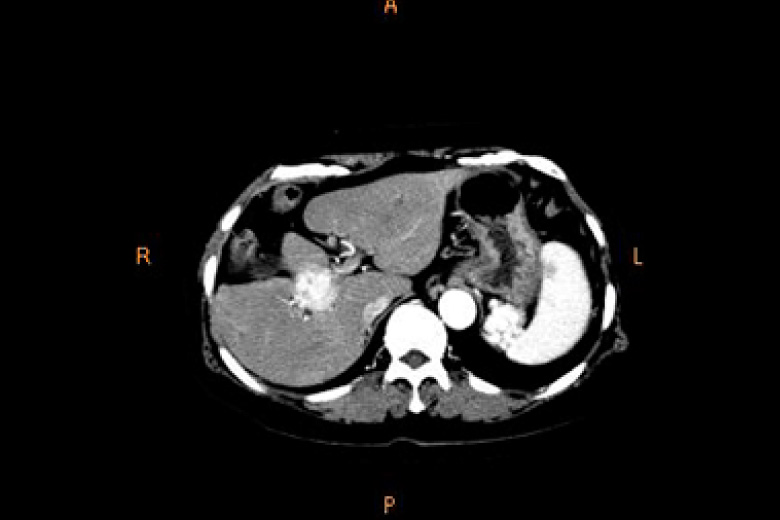

肝腫瘍

X線CT

2台のマルチスライスCT(320列、64列)にて検査を行っております。

CTはX線管と検出器が体の周りを360°回転しコンピュータ処理により画像を作成します。

頭部・胸部・腹部・四肢など全身の撮影ができ、心臓(冠動脈)などの撮影も可能です。

320列CTにより全身をより短時間で撮影できるようになり、患者さんの負担が少なくなりました。また、320列CTでは16cmの範囲(頭部や心臓など)を1回転で撮影できます。